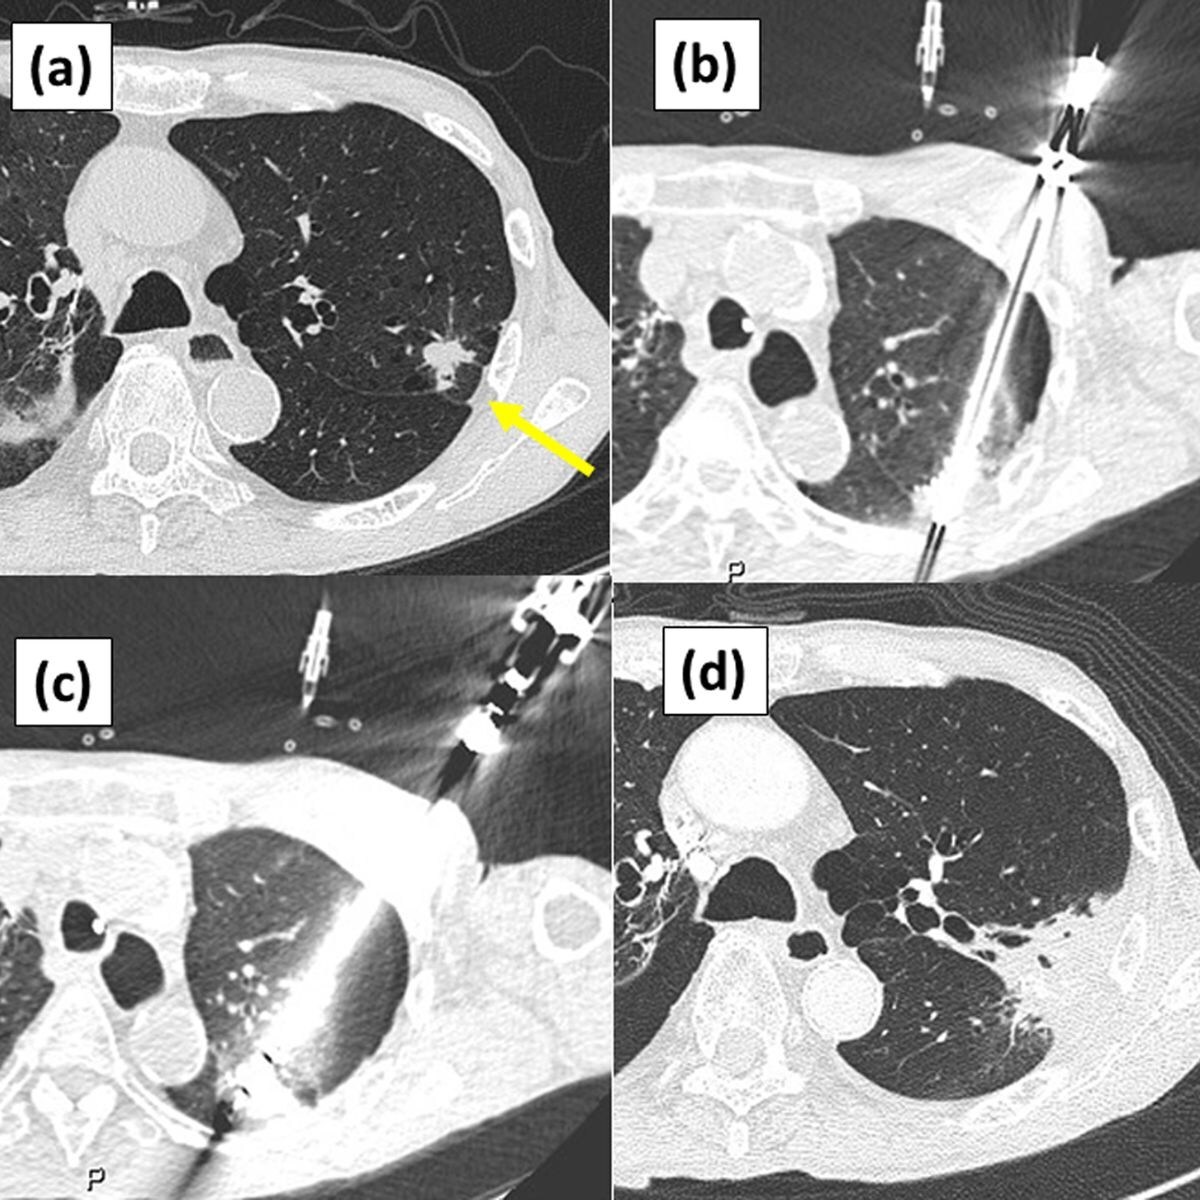

1 Image citation: "Figure 2 from Nomori H, Yue C, Iguchi H, Kashihara K, Wada R, Saito T. Long-term outcomes of combination therapy with stereotactic body radiation therapy plus cryoablation using liquid nitrogen for stage I non-small cell lung cancer with tumors ≥ 2 cm. PLOS ONE. 2025; 5:1–12. https://doi.org/10.1371/journal.pone.0332893, distributed under the terms of the Creative Commons Attribution 4.0 International License (CC BY 4.0)"

The objective of the independent retrospective observational study was to evaluate the effectiveness of combining SBRT with cryoablation for treating stage I NSCLC tumors ≥2 cm, given the limitations of local control and survival rates with SBRT monotherapy. 64 patients with tumors of mean diameter of 2.7 ± 0.5 cm and a range of 2.0–4.0 cm were treated with SBRT, followed by cryoablation. The median follow-up duration was 74 months, with a range of 3-111 months.